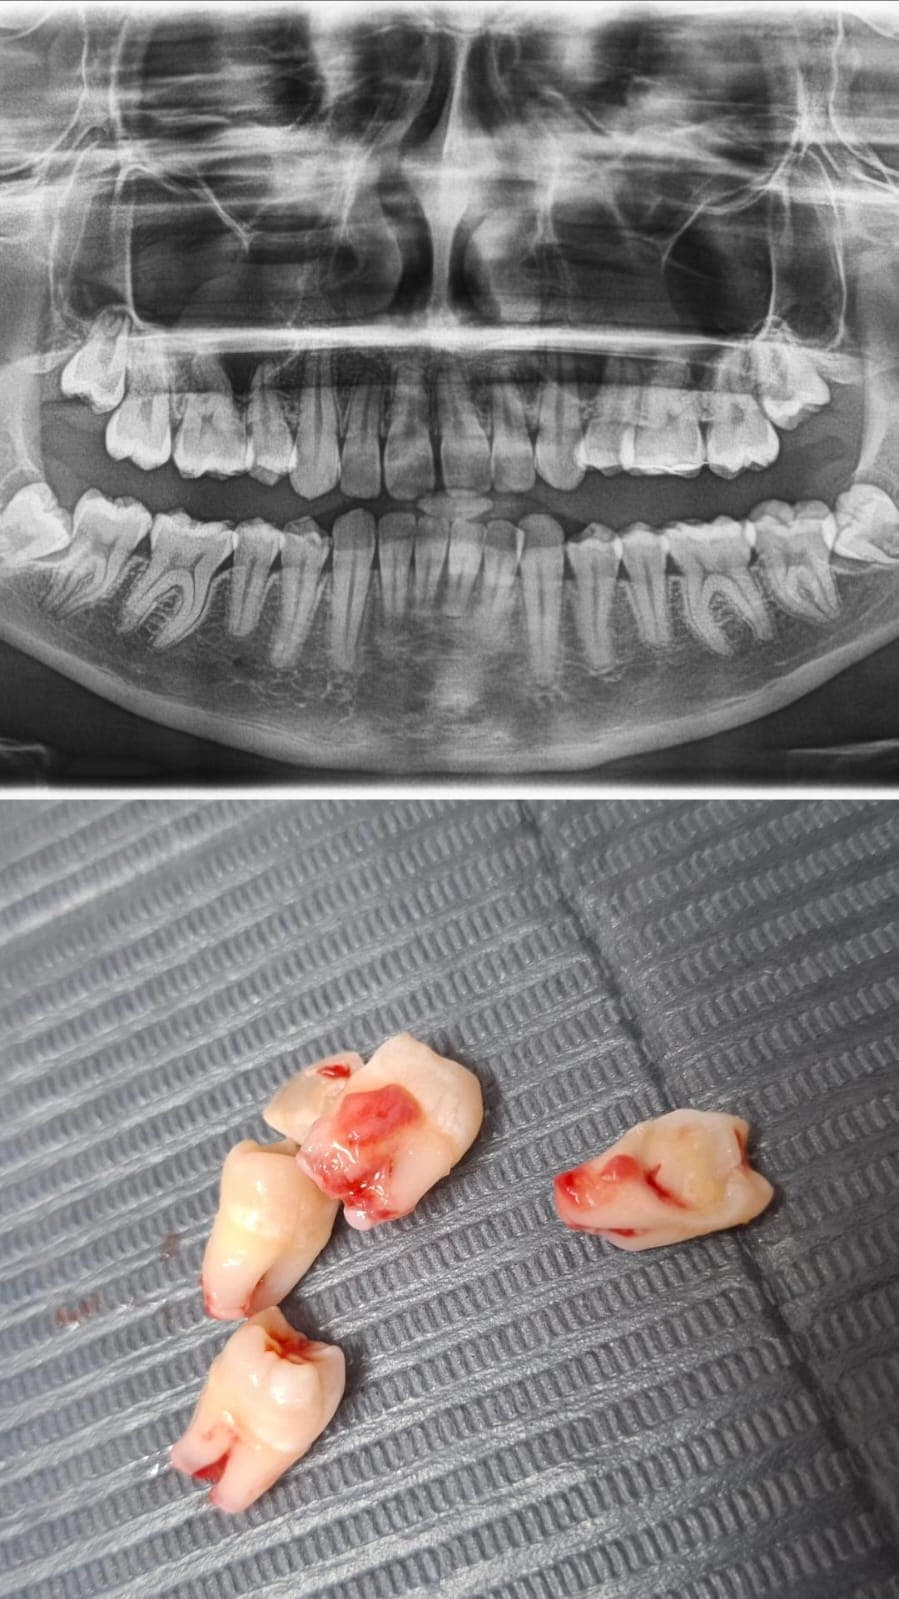

Retiro indoloro de piezas dentales que no pueden ser restauradas.

Procedimientos quirúrgicos especializados con mínima molestia y rápida recuperación.

Conoce algunos de los tratamientos realizados en nuestra clínica. Excelencia y dedicación en cada sonrisa.